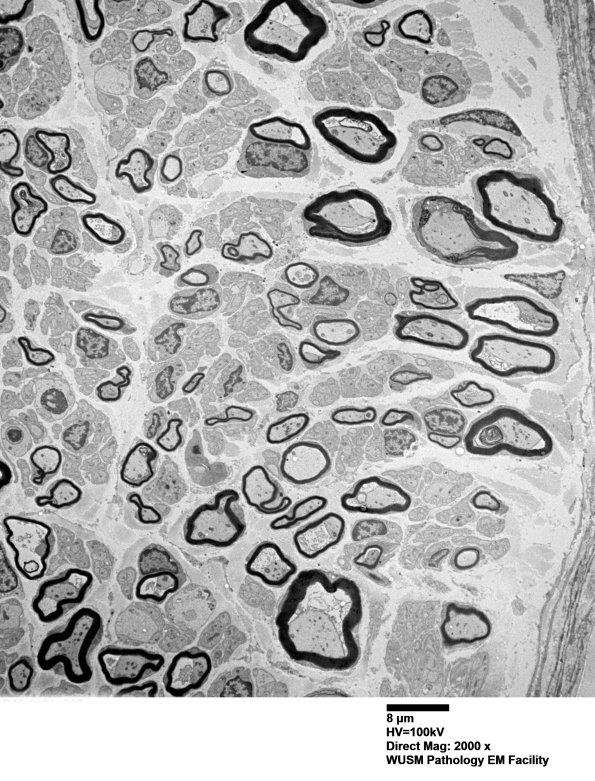

These low magnification images show developing bimodal populations of large and small myelinated axons which look discrete